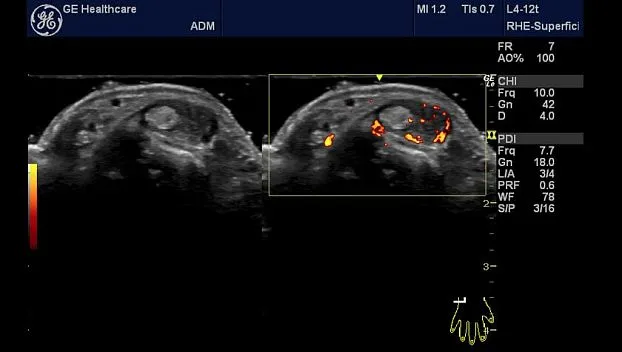

Клинические изображения

- Стандартные режимы сканирования: В-режим, М-режим, цветовое допплеровское картирование, энергетический допплер (включая направленный), импульсно-волновой допплер

- Стандартные режимы сканирования: В-режим, М-режим, цветовое допплеровское картирование, энергетический допплер (включая направленный), импульсно-волновой допплер

- Ангиология

- Ревматология

- L4-12t-RS Линейный датчик, широкополосный, мультичастотный с диапазоном частот 4,2-13,0 МГц и с 4 программируемыми кнопками. Клиническое применение: периферические сосуды, поверхностно расположенные органы и структуры, скелетно-мышечные, нервные блокады, плевра, офтальмология и контроль иглы

Систему отличает наличие датчиков со сверхвысокими частотами сканирования, эталонная чувствительность доплеровских режимов для сосудистых исследований, в том числе наиболее сложных транскраниальных, а также высокая частота кадров, которая необходима для качественных кардиологических исследований.